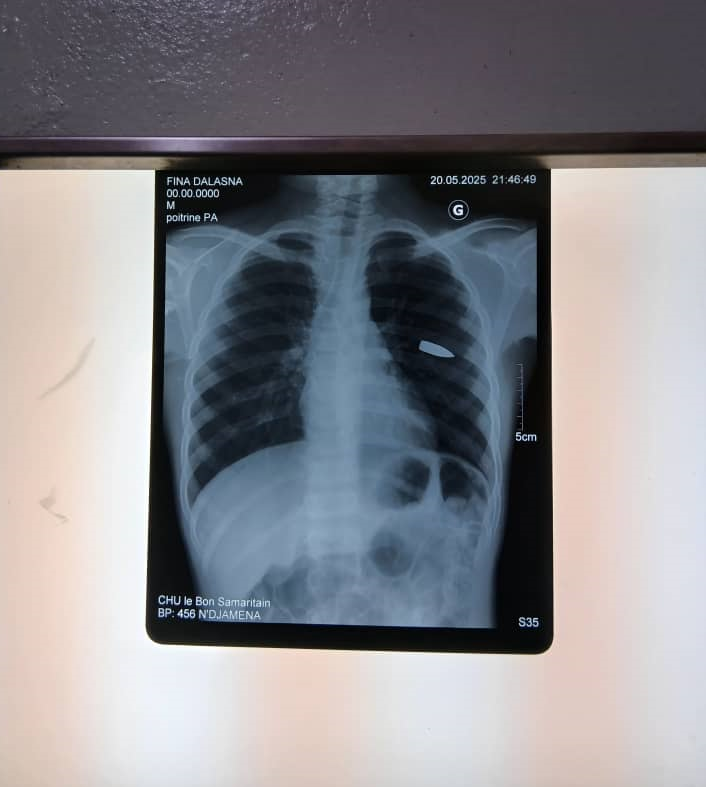

Écroulée et maculée de sang, aussitôt, la victime de 12 ans a été transportée rapidement au centre Hospitalo-universitaire, Le bon Samaritain de Walia dans le même arrondissement pour y recevoir les soins nécessaires.

Selon le géniteur de l’enfant au chevet de son enfant, les équipes médicales de cette structure ont indiqué que la balle de grand calibre, logée sous la colonne vertébrale, ne doit pas être extraite pour le moment, sauf évolution de la situation, pour y déterminer.